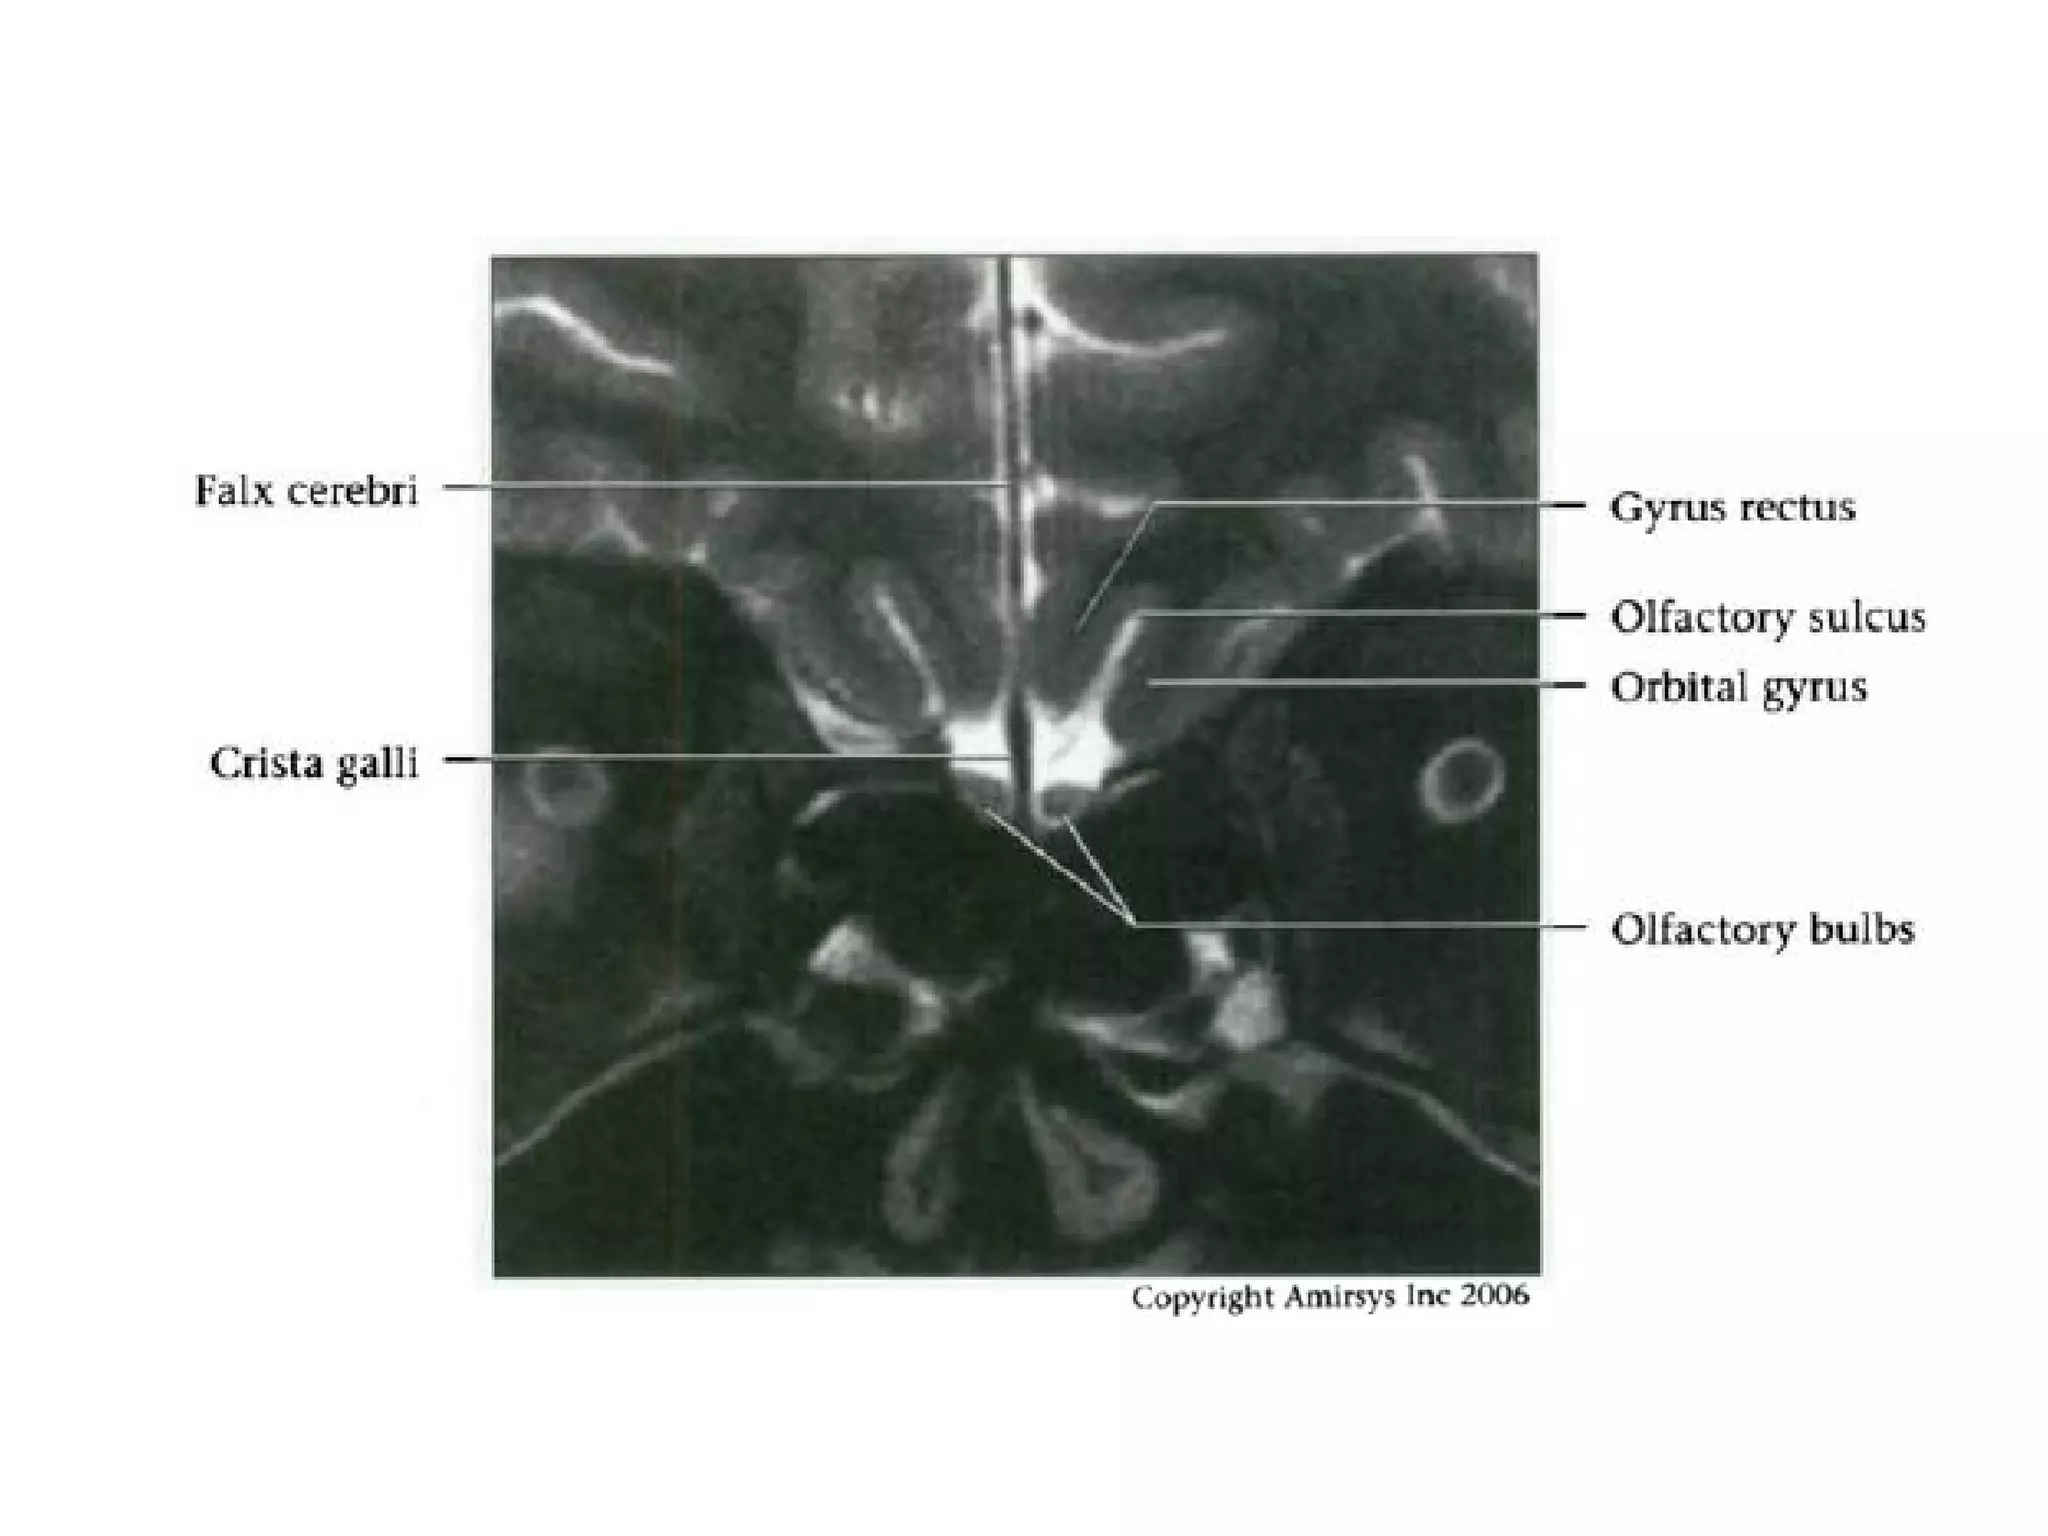

• Unlike most cranial nerves, the olfactory nerve consists

of white-matter tracts and is not surrounded by Schwann

cells

• The neurosensory cells for smell reside in the olfactory

epithelium along the roof of the nasal cavity

• The axons of these cells extend through the cribriform

plate of the ethmoid bone into the olfactory bulb at the

anterior end of the olfactory nerve

• The nerve then courses posteriorly through the anterior

cranial fossa in the olfactory groove

• Posterior to the olfactory groove, the cisternal segment

of the nerve runs below and between the gyrus rectus

and the medial orbital gyrus

RadioGraphics 2009; 29:1045–1055

Cranial Nerve I:

The Olfactory Nerve

• These secondary axons in the olfactory nerve

eventually terminate in the inferomedial temporal

lobe, uncus and entorhinal cortex

• To avoid confusing the olfactory nerve with the

gyrus rectus on axial images, it is important to

remember that the olfactory nerve is situated

deep in the olfactory groove, inferior to the gyrus

rectus

• Coronal images are easiest to interpret because

the nerves are seen in cross section

Olfactory nerve.

Axial and coronal 0.8-mm-thick SSFP MR images show the olfactory nerve (white arrow)

within the CSF-filled olfactory groove and the optic nerve (black arrow) ringed by

highsignal-intensity CSF within the dural sheath.

Coronal 1.0-mm-thick SSFP MR image shows the cisternal segment of the olfactory

nerve (arrow), which is located inferior to and between the gyrus rectus (r) and the

medialorbital gyrus (o).